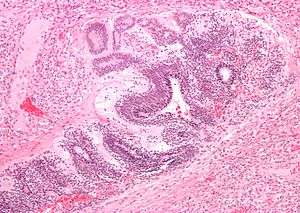

| Micrograph of the primitive neuroepithelium of an immature teratoma of the mediastinum. H&E stain. | |